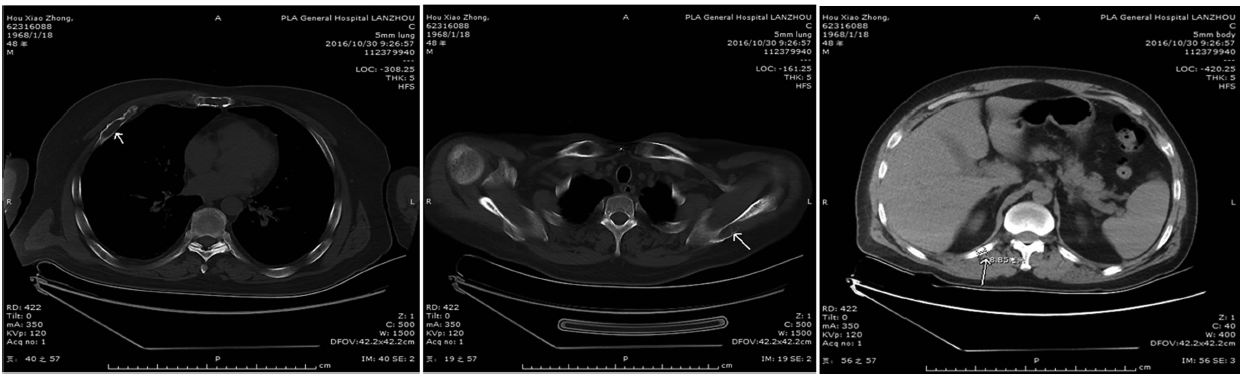

大灶性骨髓瘤是一种非常罕见的浆细胞瘤,目前对其生物学行为认识有限,易误诊为经典多发性骨髓瘤及其他髓外浆细胞瘤。现报道1例大灶性骨髓瘤的临床诊治经过,并对其临床特点及鉴别诊断进行探讨。